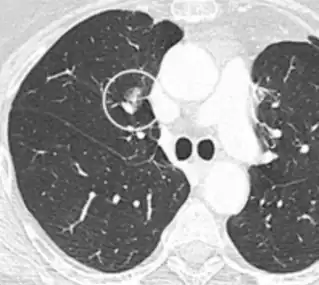

Thin slice and maximal intensity projection of a lung nodule, the latter better visualizing vascular convergence.[9]

• Vascular convergence is where vessels converge to a nodule without adjoining or contacting the edge of the nodule, and is mainly seen in peripheral subsolid lung cancers.[9] It reflects angiogenesis.[9]